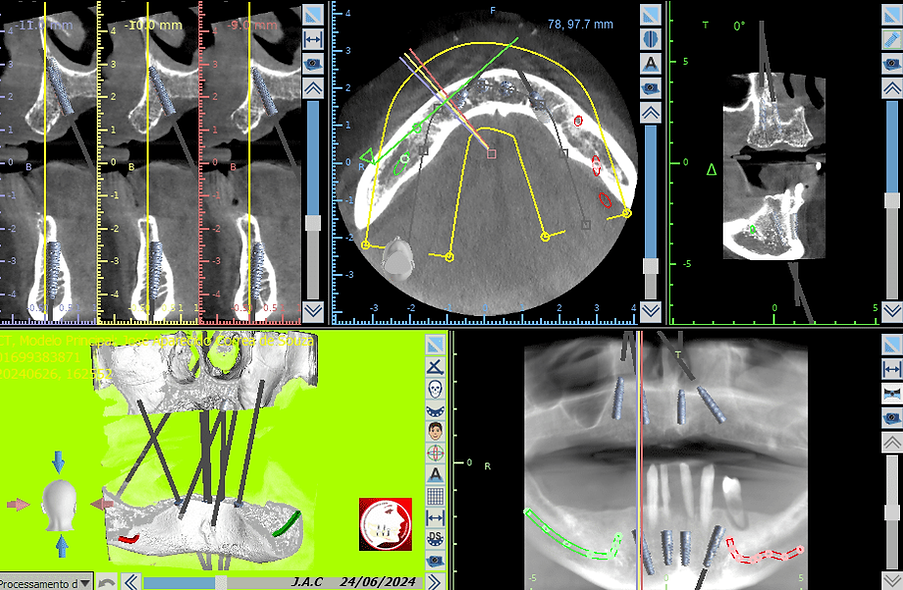

Planejamento Digital e Tecnologia 3D

Cada caso é planejado com exames detalhados e softwares avançados, permitindo posicionamento preciso dos implantes e maior previsibilidade nos resultados.

isso proporciona mais segurança, conforto e resultados duradouros para o paciente.